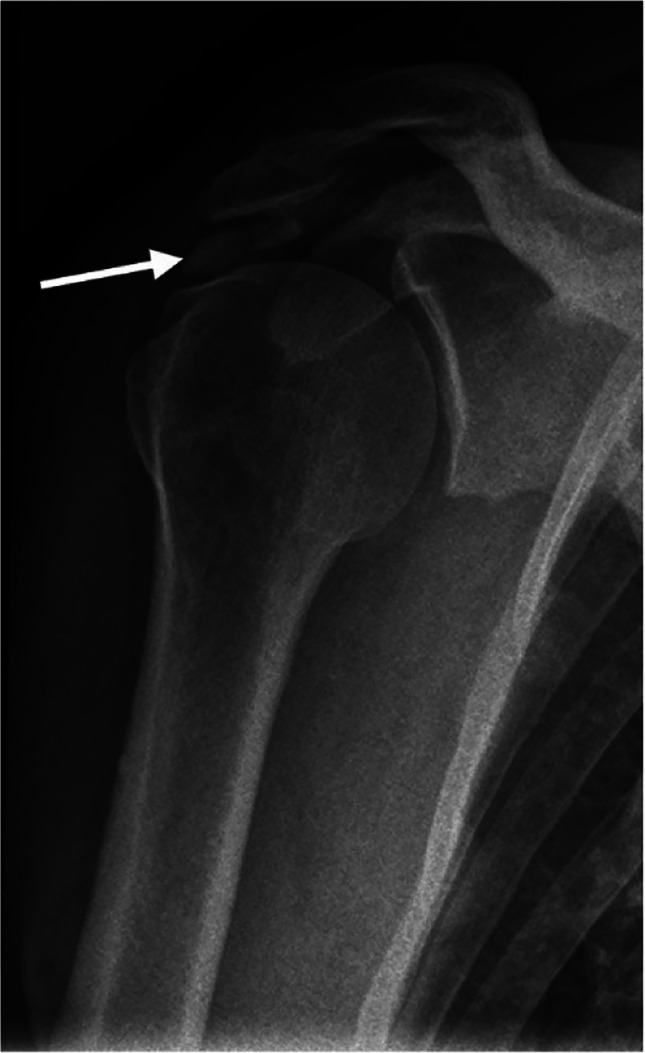

目的:研究疑似肩峰下撞击综合征(SIS)患者的特定x线表现与患者报告的肩部疼痛和残疾之间的关系。材料和方法:本横断面研究采用前瞻性研究的基线数据。研究人群包括年龄在18至63岁之间,因怀疑SIS而转诊到骨科诊所的患者。首次到骨科就诊前的影像学检查包括肩峰下钙化、肩峰形态特征(即肩峰类型和骨刺)、肩锁骨关节炎、既往肩关节脱位的迹象(Bankart/Hill-Sachs病变)和建筑测量(即肩峰倾斜、肩峰指数和肩峰外侧角)。采用牛津肩关节评分(OSS)对患者首次到公立骨科就诊时或SIS手术前的问卷回答进行肩部疼痛和残疾评估。低OSS被定义为具有评分结果:人群包括825例患者。从x线检查到完成问卷的中位时间为9天(SD = 27.1)。在校正分析中,我们发现侧骨刺,特别是鸟喙型(OR = 2.24 (95% CI 1.36-3.71)), Bankart/Hill-Sachs病变(OR = 2.49 (95% CI 1.38-4.48))和肩峰倾斜bbb35°(OR = 0.62 (95% CI 0.41-0.94))具有统计学意义。女性(OR = 2.25 (95% CI 1.59-3.18))也与低OSS相关。结论:就患者报告的肩部疼痛和残疾的相关性而言,侧刺,重点是鸟喙型,Bankart/Hill-Sachs病变和肩峰倾斜bbb35°,在临床上似乎很重要。

Materials and methods: This cross-sectional study used baseline data from a prospective study. Study population included patients age 18 to 63 years, referred to orthopaedic clinic on suspicion of SIS. Radiographic findings before first visit to a department of orthopaedic surgery comprised subacromial calcifications, acromial morphological characteristics (i.e. acromial type and spur), acromioclavicular osteoarthritis, signs of previous glenohumeral dislocation (Bankart/Hill-Sachs lesions), and architectural measures (i.e. acromial tilt, acromion index, and lateral acromial angle). Shoulder pain and disability were evaluated using the Oxford Shoulder Score (OSS) from patient's response to a questionnaire at first visit to the public department of orthopaedic surgery or before surgery for SIS. A low OSS was defined as having a score < 25. Associations between the radiographic findings and low OSS were analysed using logistic regression.

Results: The population comprised 825 patients. Median time between radiographic examination and completion of the questionnaire was 9 days (SD = 27.1). In adjusted analysis, we found a statistically significant association for lateral spur especially birdbeak type (OR = 2.24 (95% CI 1.36-3.71)), Bankart/Hill-Sachs lesion (OR = 2.49 (95% CI 1.38-4.48)), and acromial tilt > 35° (OR = 0.62 (95% CI 0.41-0.94)). Female sex (OR = 2.25 (95% CI 1.59-3.18)) was also associated with low OSS.

Conclusion: In terms of associations with patient-reported shoulder pain and disability, lateral spurs, with emphasis on birdbeak type, Bankart/Hill-Sachs lesions, and acromial tilt > 35°, seemed clinically important.